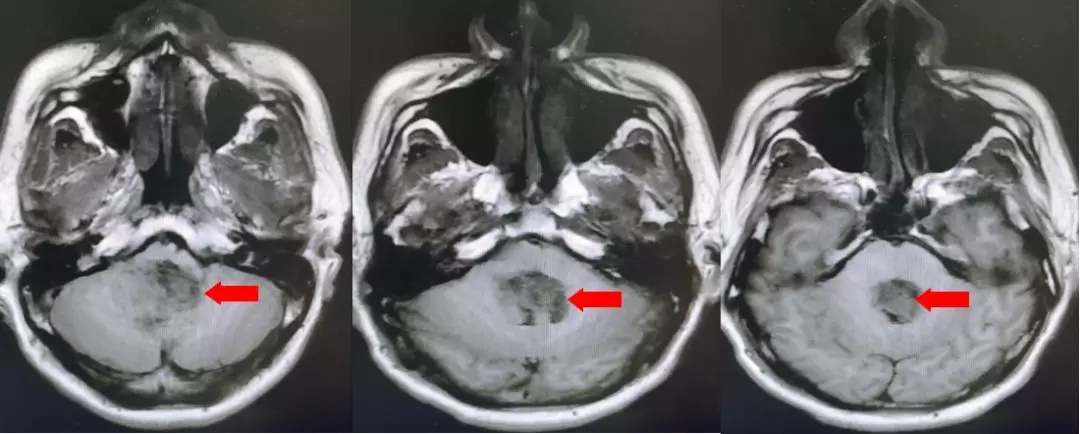

颅脑核磁T1W1成像

第四脑室内见一巨大形态不规则的异常信号影,肿瘤信号不均匀,T1W1呈略低信号影,T2W1呈稍高及高信号影,增强扫描可见肿瘤不均匀明显强化。肿瘤充满整个四脑室,大小约44*37*55mm,上方接近四脑室顶部,下方至颈2脊髓平面上方,已经部分侵袭桥脑、延髓,局部边界不清,无明显间隙,脑干局部明显受压变形。肿瘤上方脑室系统扩张,出现梗阻性脑积水征象。

影像诊断:1.第四脑室内占位性病变,室管膜瘤可能性大;2.梗阻性脑积水。